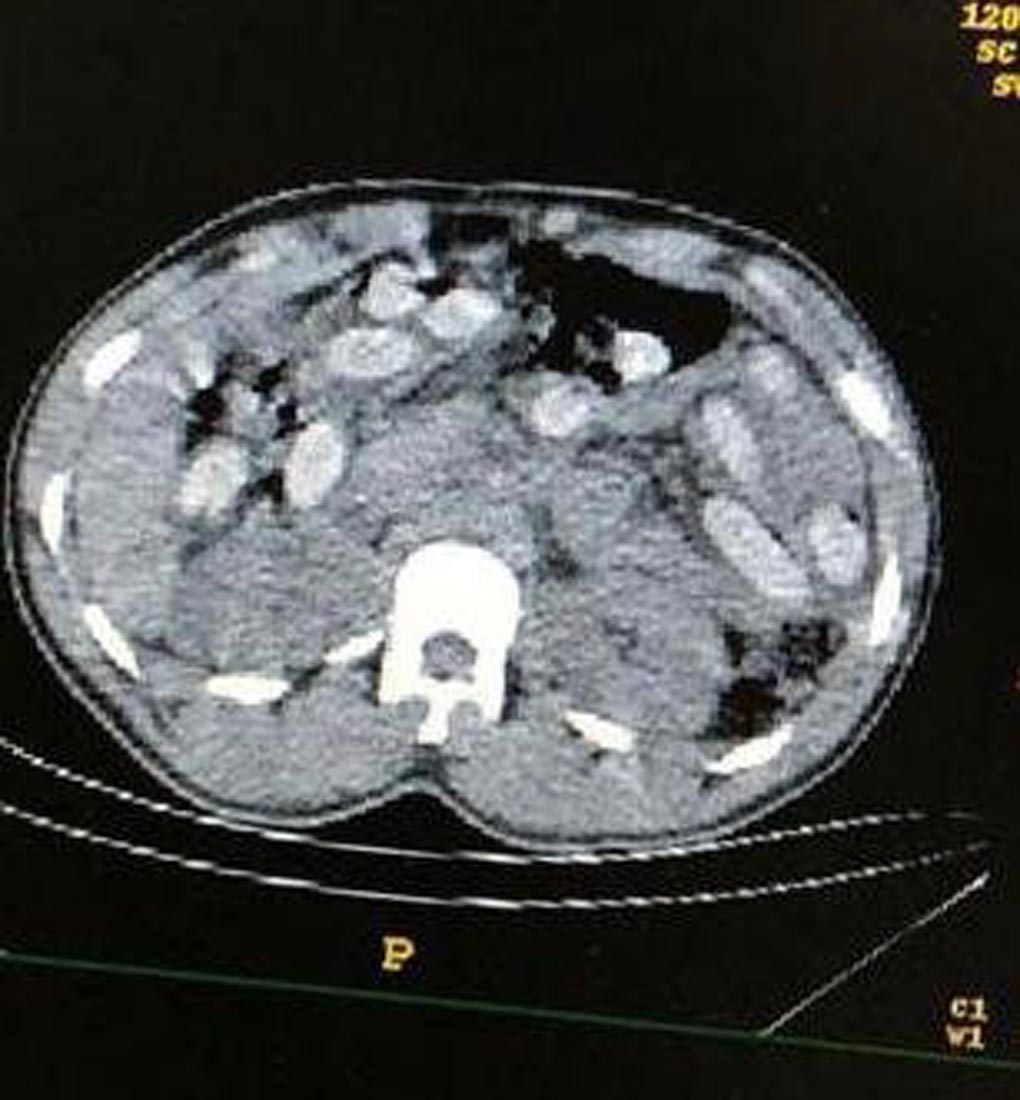

Sağlık taramasından geçen şüphelilerin tomografileri çekildi. 3 kişinin mide ve bağırsaklarında tespit edilen uyuşturucu, doktorlar tarafından çıkarıldı. Şüpheli S.E.Z.'nin mide ve bağırsaklarından 2 kapsül halinde 74,36 gram metamfetamin, 18 kapsül halinde 172,8 gram eroin, Y.Y.B' den 3 kapsül halinde 115,05 gram metamfetamin, 39 kapsül halinde 351,18 gram eroin ve A.S.G. isimli şüpheliden ise 2 kapsül halinde 75,83 gram metamfetamin çıktı.